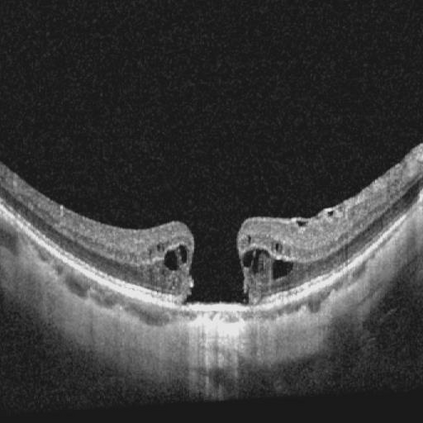

Ophthalmology relies heavily on detailed image analysis for diagnosis and treatment planning. While large vision-language models (LVLMs) have shown promise in understanding complex visual information, their performance on ophthalmology images remains underexplored. We introduce LMOD, a dataset and benchmark for evaluating LVLMs on ophthalmology images, covering anatomical understanding, diagnostic analysis, and demographic extraction. LMODincludes 21,993 images spanning optical coherence tomography, scanning laser ophthalmoscopy, eye photos, surgical scenes, and color fundus photographs. We benchmark 13 state-of-the-art LVLMs and find that they are far from perfect for comprehending ophthalmology images. Models struggle with diagnostic analysis and demographic extraction, reveal weaknesses in spatial reasoning, diagnostic analysis, handling out-of-domain queries, and safeguards for handling biomarkers of ophthalmology images.